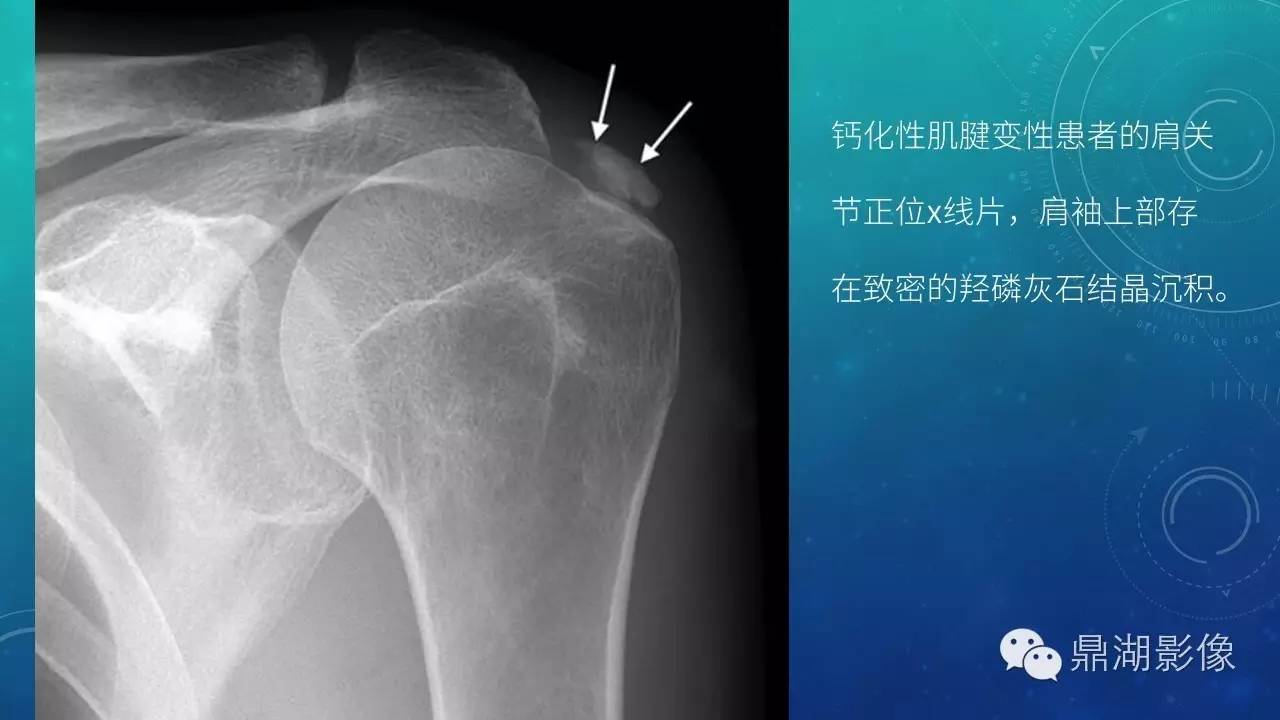

【PPT】软组织钙化(的鉴别)